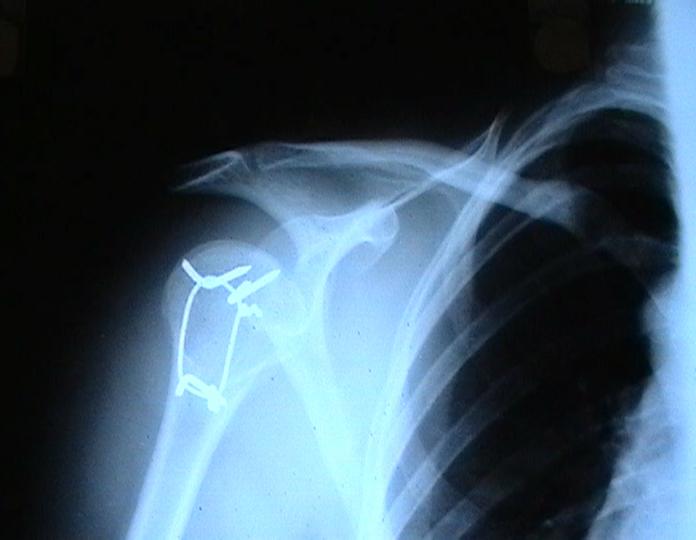

Мужчина 25 лет 16 августа 2002 г. в автоаварии получил перелом шейки плеча (снимок 1); 5 сентября в городской больнице выполнен остеосинтез пластинкой (снимок 2).К настоящему времени попал к нам на разработку ввиду выраженной контрактуры плечевого сустава. В течение последнего месяца беспокоят умеренные боли в области плечевого сустава, усиливающиеся при разработке, еще и торчит край пластинки. Нынешняя рентгенологическаякартина на снимках 3 и 4. Головка плеча уменьшается, сращение сомнительное.Кроме удаления пластинки, что еще на сегодня целесообразно сделать?Заранее спасибо.

Согласен с вашим мнением -асептический некроз головки плеча. Есть ли у вас надежды на реваскуляризацию головки ? Если надеетесь, то имеет смысл продолжать физио, если нет, то следует думать опротезировании.

I think the AVN is at least stage 3 with deformity of the head. I would advise a removal of implant and a cementless humeral head replacement. Or if you have the experience and the implant, as well as adequate bone stock, maybe a resurfacing prosthesis like the Copeland shoulder. I am not sure if you can do it one or two stages. You can perhaps do it in one stage if there is no sign of infection and if the patient condition allows it. You should not worry too much about age since this is a non